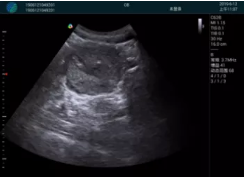

腺體內(nèi)部清晰顯示一低回聲塊影,形態(tài)不規(guī)則,邊界模糊,邊緣呈毛刺狀,內(nèi)部見砂礫樣鈣化